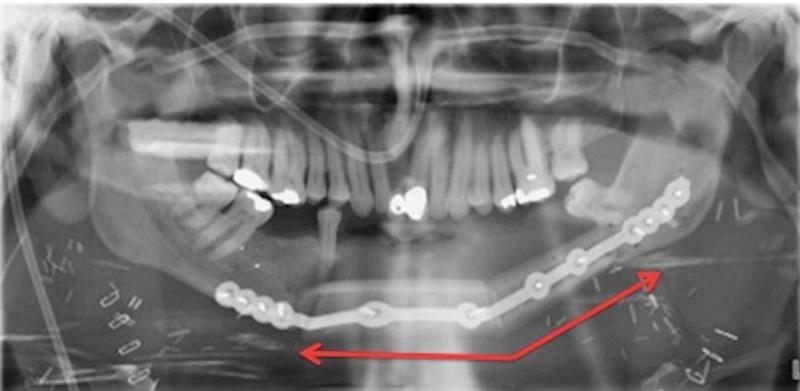

Ameloblastoma is a locally aggressive tumor that most commonly arises in the mandible. It has a high rate of recurrence if inadequately excised. We report a case of a patient who developed recurrence of his ameloblastoma in his fibula flap mandibular reconstruction despite clear resection margins 23 years after resection. This is the first reported case of recurrent ameloblastoma in a neo-mandible reconstruction in the setting of negative margins. We discuss its surgical management using digital planning and reconstruction using a contralateral free fibula flap. Ameloblastoma is a locally aggressive entity that requires complete excision. Recurrence can even occur in the reconstruction, which can present a challenge to manage. Consideration should be given to repeat excision and second osseous flap reconstruction.

成釉细胞瘤是一种具有局部侵袭性的肿瘤,最常发生于下颌骨。如果切除不充分,其复发率很高。我们报告一例患者,在切除23年后,其腓骨瓣下颌骨重建中的成釉细胞瘤出现复发,尽管切除边缘清晰。这是首例在切缘阴性情况下新下颌骨重建中复发性成釉细胞瘤的报道病例。我们讨论了使用数字规划进行手术管理以及使用对侧游离腓骨瓣进行重建的情况。成釉细胞瘤是一种需要完整切除的局部侵袭性病变。复发甚至可能发生在重建过程中,这给治疗带来了挑战。应考虑再次切除和二期骨瓣重建。